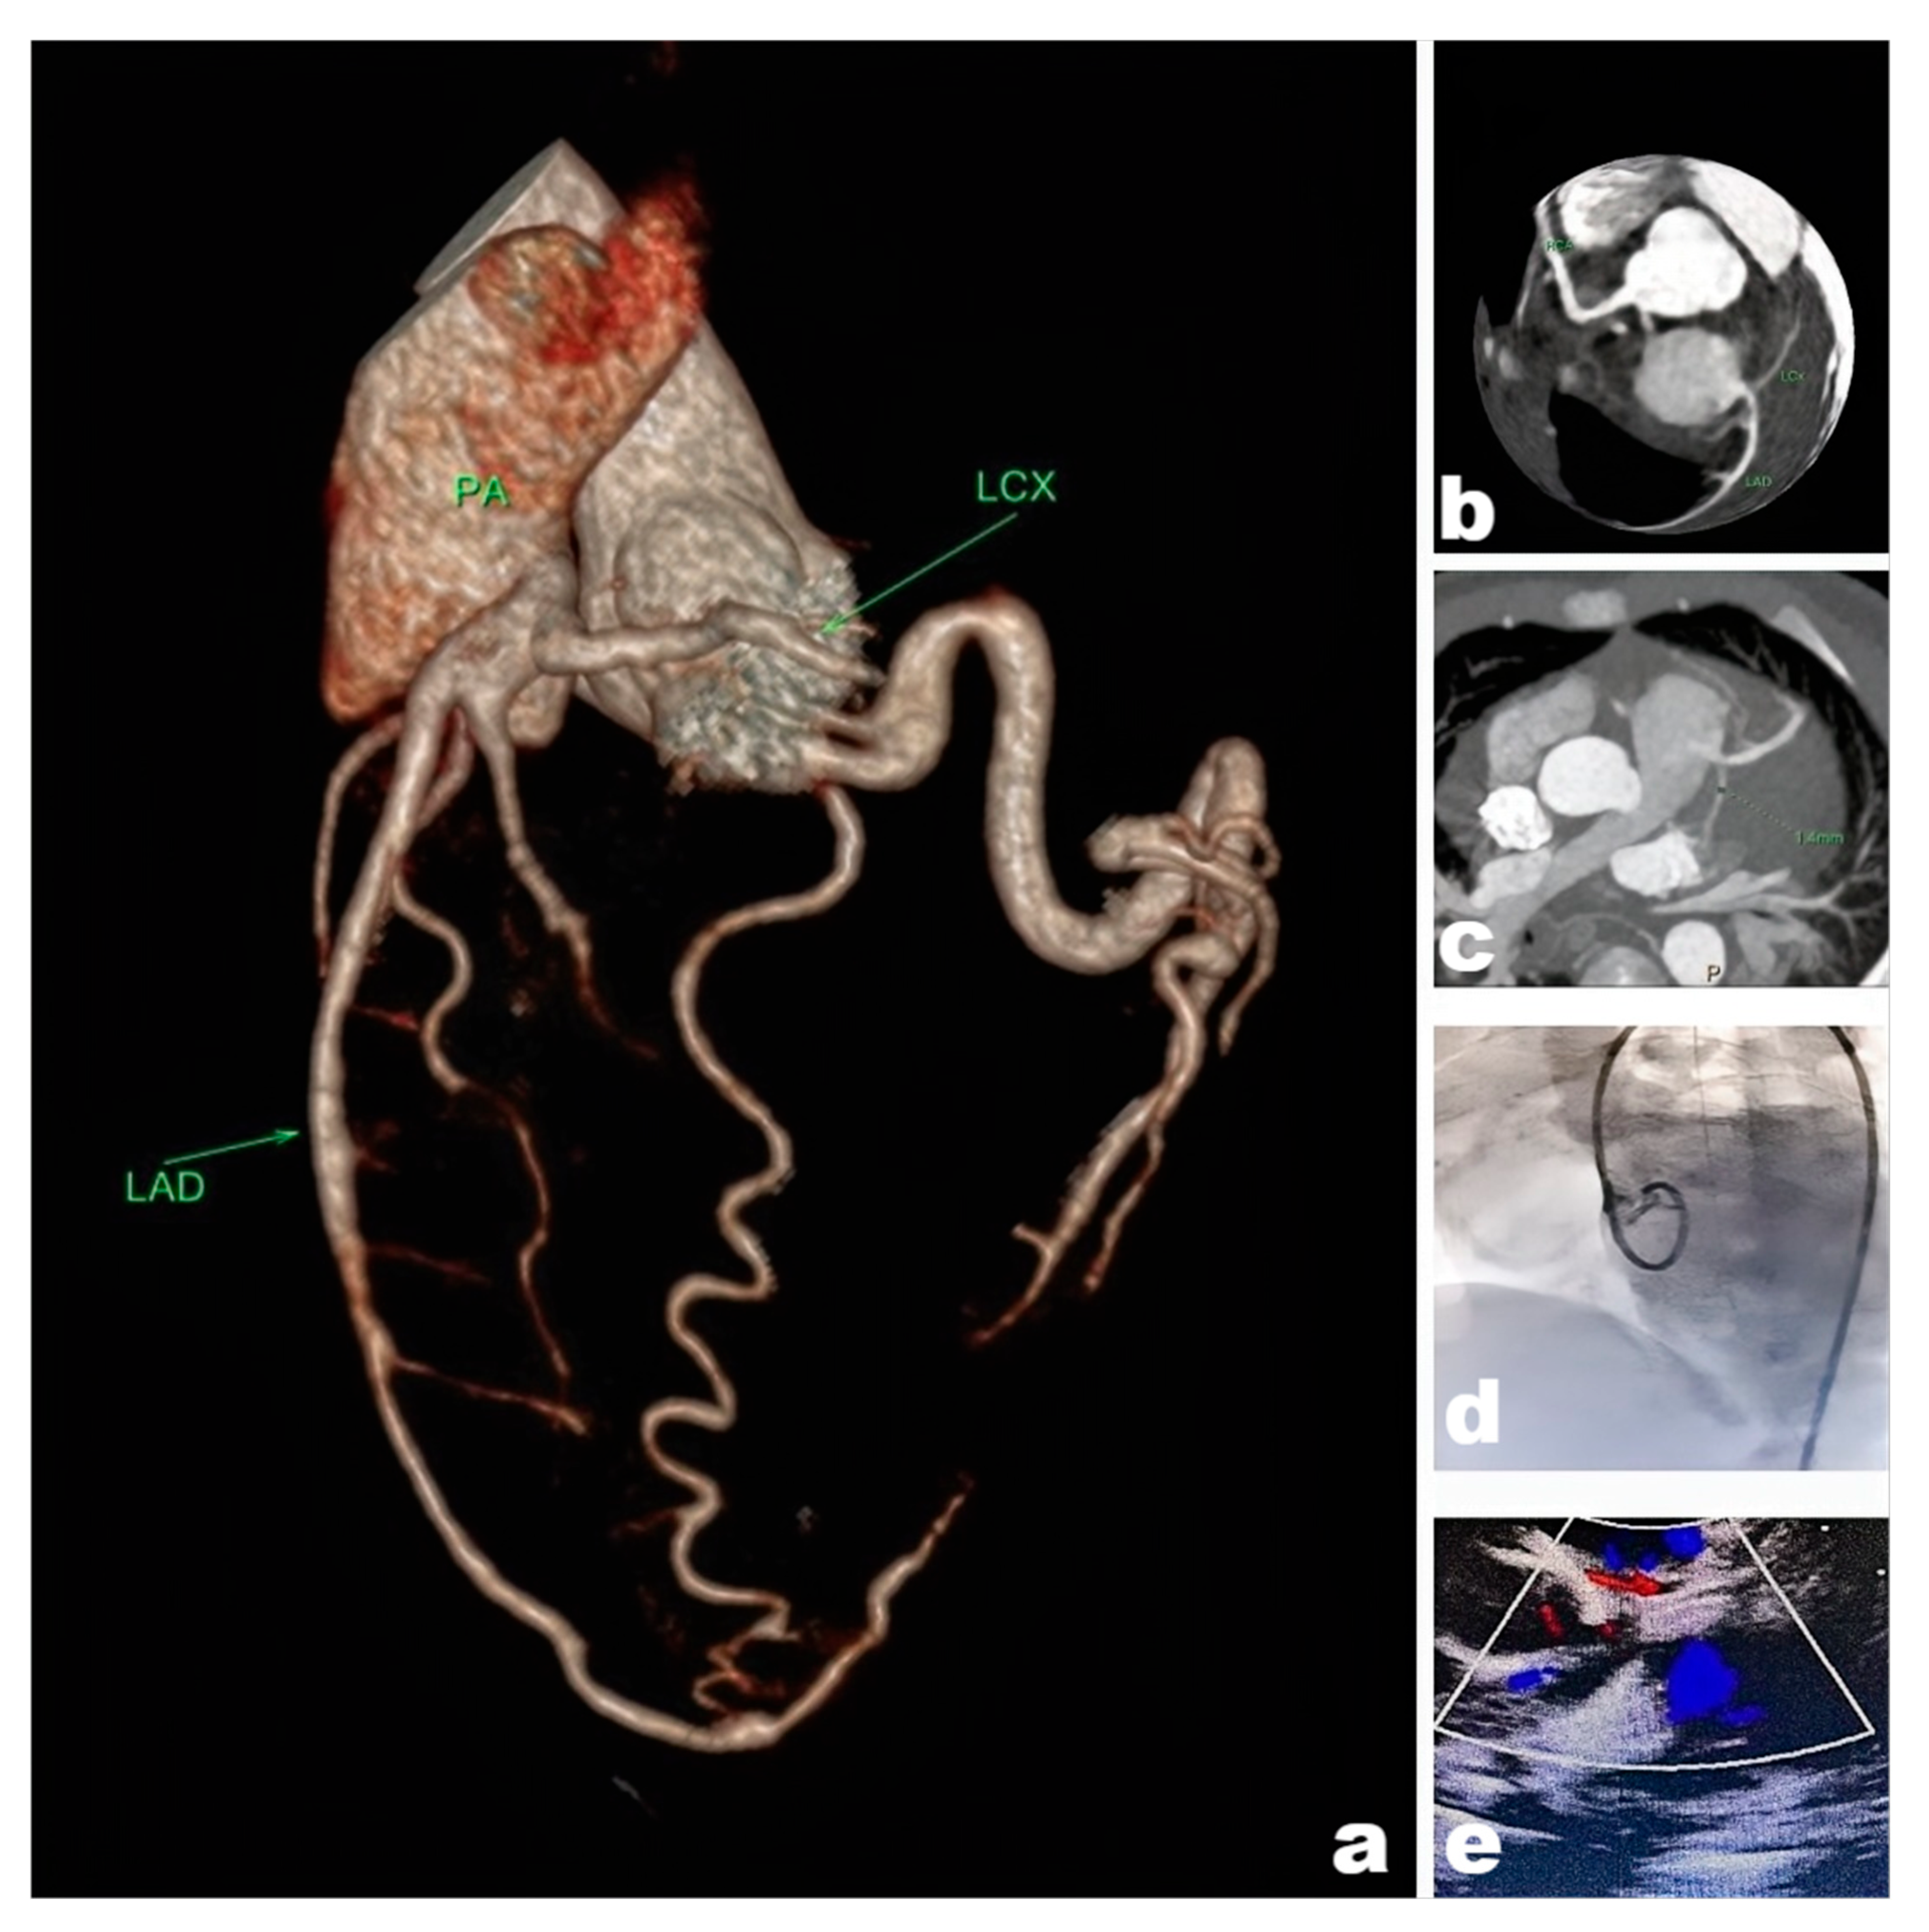

All patients underwent electrocardiogram (ECG), Echo, chest radiography. CT angiography (CTA) was performed in the majority of cases to assess coronary artery anatomy, including abnormal vessel lengths and diameters. Although invasive coronary angiography remains the diagnostic gold standard, its risks are particularly elevated in infants and young children, including radiation exposure, anesthetic drugs, and contrast agent-related complications. Therefore, when non-invasive imaging modalities provide sufficient diagnostic information for surgical planning, we typically avoid coronary angiography to minimize risks. Multidisciplinary discussions were conducted for complex cases. We usually have some discussions about the complex situation. Representative imaging findings are illustrated in Fig. 1. In addition, myocardial nuclear imaging and magnetic resonance coronary angiography (MRCA) can be used as complementary tests, but not as routine tests [3].

Figure 1: Picture (a). CTA reconstruction revealed an Anomalous origin of the left coronary artery from the pulmonary artery. (b,c). Images of coronary suggesting that the left coronary artery anomaly originated from the pulmonary artery. (d). Invasive coronary angiography of the left coronary artery was disappeared, indicating that the hemodynamic abnormality was present in the left coronary artery. (e). Ultrasound suggesting that abnormal blood flow signals were present in the pulmonary artery, the “blood-stealing syndrome” was happened.